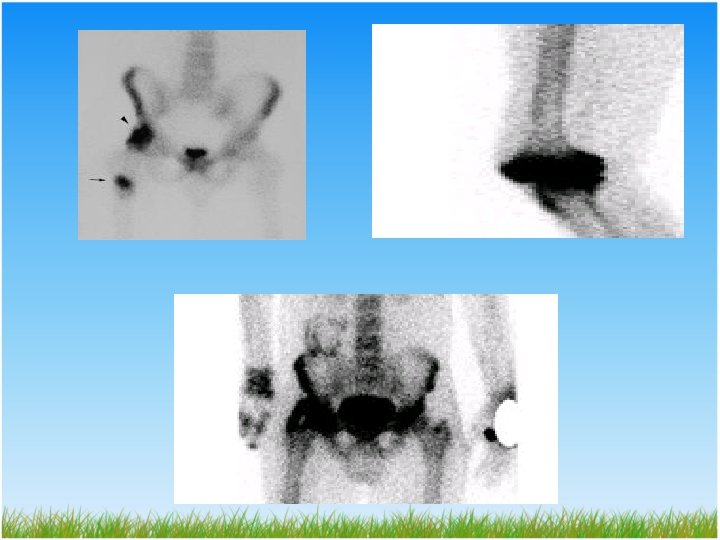

TANI Radyodiagnostik • Direkt grafi • Ultrasonografi • Bilgisayarlı tomografi(BT) • Magnetik rezonans(MR) • Üç fazlı kemik sintigrafisi

TANI • Üç fazlı kemik sintigrafisi – Erken tanı – İlk haftadan sonra görüntüleme sağlar – Teknisyum 99 metilen difosfonat kullanılır – İlk haftalarda enflamatuar, travmatik ve dejeneratif süreçleri ayıramayabilir – Maturasyon takibinde altın standartdır